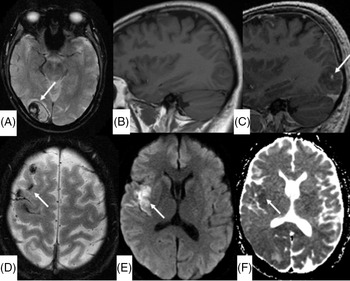

A 53-year-old man who underwent recent mitral valve repair and tricuspid valve annuloplasty 3 months prior presented with transient mild left-sided facial droop and dysarthria. He had a National Institute of Health Stroke Scale (NIHSS) of 1. Initial unenhanced CT and CT angiogram (Figure 1A and B) demonstrated acute infarct in the right insula secondary to a filling defect in right distal middle cerebral artery (MCA). MRI vessel wall imaging was performed 12 h after initial CT to clarify the etiology of this filling defect and was concluded an embolus as there was no evidence of wall thickening or enhancement. Limited brain sequences (Figures 1C–H) performed concurrently demonstrated high fluid-attenuated inversion recovery (FLAIR) signal in the right insula, compatible with the infarct. There was additionally unexpected sulcal T1 and FLAIR hyperintensity overlying right frontal convexity and an area of contrast blush in the right occipital lobe without other corresponding abnormality allowing for lack of diffusion weighted imaging (DWI) and blood-sensitive sequences on this first MRI. While awaiting cardiac investigations, the patient developed visual field defect, prompting the second MRI brain with contrast (Figure 2). This MRI demonstrated a parenchymal hematoma in the right occipital lobe, with a focal area of enhancement centrally. The sulcal T1 and FLAIR hyperintensity were confirmed as blood products on the susceptibility weighted imaging (SWI) sequence, and there was restricted diffusion in the right insula, confirming the right MCA infarct. A subsequent transesophageal echocardiography demonstrated vegetation in the heart valves and he was commenced on moxifloxacin and doxycycline for 6 weeks. A digital subtraction angiography (DSA) was performed to exclude a mycotic aneurysm causing the parenchymal hematoma with this knowledge and was negative. He remained well without progression or development of new focal neurological deficit and was discharged with an NIHSS score of 0, 12 days after initial presentation.

Figure 2: (A) Axial SWI at the level of the right occipital lobe shows interval development of a parenchymal hematoma. (B and C) Pre- and post-gadolinium sagittal T1-weighted image shows focal contrast enhancement in the right occipital hematoma, denoting the “conventional” spot sign. (D) Axial SWI demonstrates hemosiderin staining corresponding to the intermediate T1-weighted and high FLAIR signal seen on baseline imaging, confirming blood products in the subarachnoid space. Axial DWI sequence (E) and apparent diffusion coefficient map (F) demonstrate restricted diffusion in the right insula, confirming an embolic infarct.

The “spot” sign was first described on CT angiography by Wada et al. as a focus of contrast extravasation within a hematoma, shown to be predictor of hematoma expansion. Reference Wada, Aviv and Fox1 Multiple case reports and studies have assessed and reported on the analogous MRI spot sign in intracerebral and subdural hematoma. Reference Cutsforth-Gregory, Black, Hoffman, Datar and Wijdicks2–Reference Allam, Sweis and Sander4 Our case is unique in that the “spot” sign was demonstrated incidentally on an MRI performed for a different indication prior to any symptoms or signal abnormality in the right occipital lobe. Although we cannot definitely exclude an infarct in the right occipital lobe without a DWI sequence on the initial MRI, there is breakdown of the blood–brain barrier leading to parenchymal hematoma in any case of hemorrhage, whether spontaneous hemorrhage, hemorrhagic transformation of an infarct or rupture of a mycotic aneurysm. DSA in this case showed no aneurysms. Further, there is a differential diagnosis to the contrast blush, such as leptomeningeal process in a patient with endocarditis. We posit that the contrast blush demonstrated on initial limited MRI heralded the parenchymal hematoma.

This has implications on clinical practice because, as with other hyperacute stroke imaging features including the dense MCA sign Reference Tomsick, Brott and Barsan5 and non-demonstration of restricted diffusion in hyperacute stroke, Reference Lefkowitz, LaBenz, Nudo, Steg and Bertoni6 the differential diagnosis of imminent parenchymal hemorrhage should be included when an unexplained contrast blush on MRI is demonstrated.